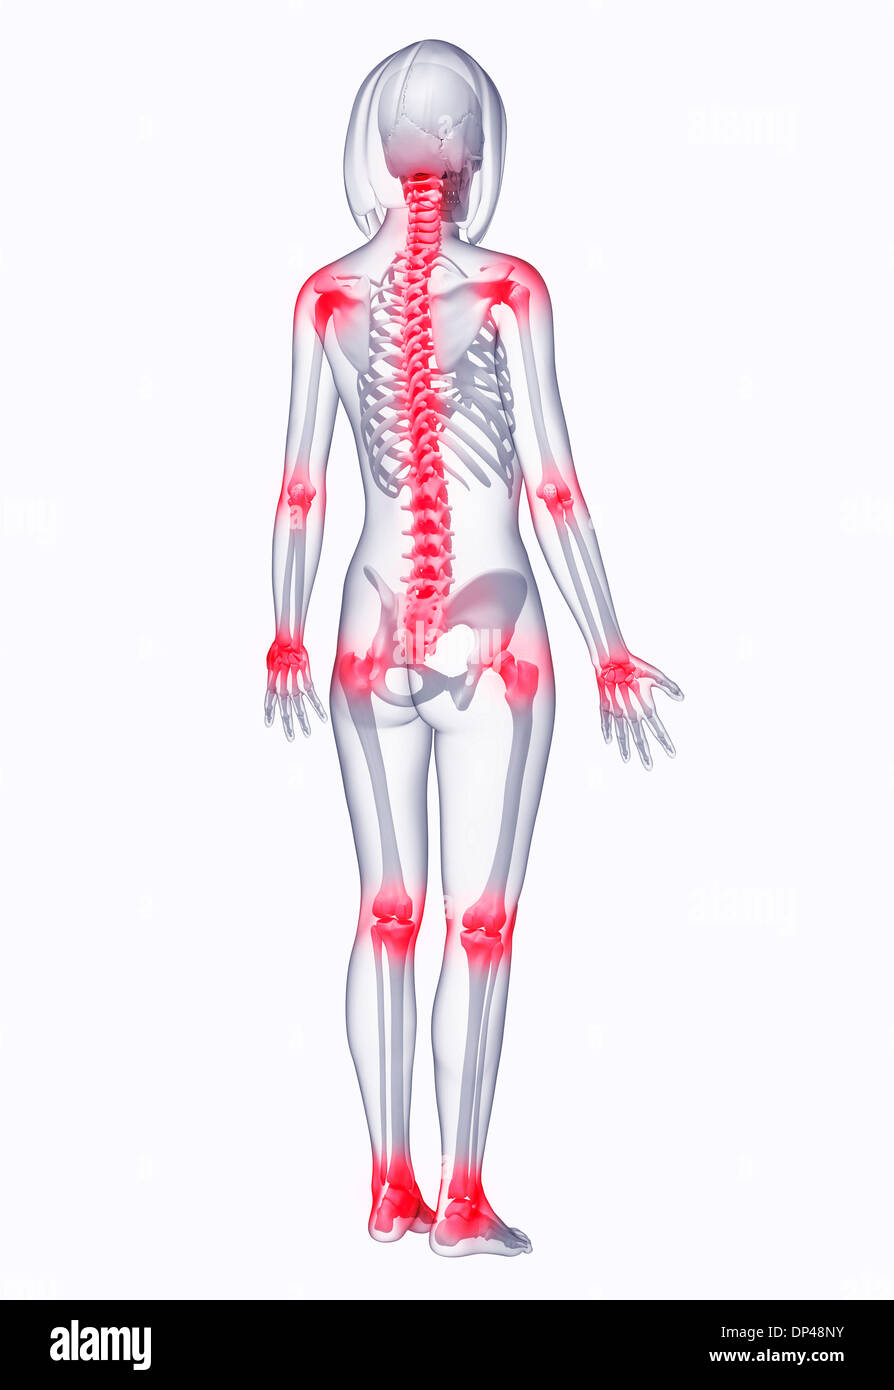

La douleur commune, artwork Banque D'Imageshttps://www.alamyimages.fr/image-license-details/?v=1https://www.alamyimages.fr/la-douleur-commune-artwork-image65261264.html

La douleur commune, artwork Banque D'Imageshttps://www.alamyimages.fr/image-license-details/?v=1https://www.alamyimages.fr/la-douleur-commune-artwork-image65261264.htmlRFDP4WBC–La douleur commune, artwork

La douleur commune, artwork Banque D'Imageshttps://www.alamyimages.fr/image-license-details/?v=1https://www.alamyimages.fr/la-douleur-commune-artwork-image65260439.html

La douleur commune, artwork Banque D'Imageshttps://www.alamyimages.fr/image-license-details/?v=1https://www.alamyimages.fr/la-douleur-commune-artwork-image65260439.htmlRFDP4T9Y–La douleur commune, artwork

La douleur commune, artwork Banque D'Imageshttps://www.alamyimages.fr/image-license-details/?v=1https://www.alamyimages.fr/la-douleur-commune-artwork-image65260401.html

La douleur commune, artwork Banque D'Imageshttps://www.alamyimages.fr/image-license-details/?v=1https://www.alamyimages.fr/la-douleur-commune-artwork-image65260401.htmlRFDP4T8H–La douleur commune, artwork

La douleur commune, artwork Banque D'Imageshttps://www.alamyimages.fr/image-license-details/?v=1https://www.alamyimages.fr/la-douleur-commune-artwork-image65251183.html

La douleur commune, artwork Banque D'Imageshttps://www.alamyimages.fr/image-license-details/?v=1https://www.alamyimages.fr/la-douleur-commune-artwork-image65251183.htmlRFDP4CFB–La douleur commune, artwork

La douleur commune, artwork Banque D'Imageshttps://www.alamyimages.fr/image-license-details/?v=1https://www.alamyimages.fr/la-douleur-commune-artwork-image65246463.html

La douleur commune, artwork Banque D'Imageshttps://www.alamyimages.fr/image-license-details/?v=1https://www.alamyimages.fr/la-douleur-commune-artwork-image65246463.htmlRFDP46ER–La douleur commune, artwork